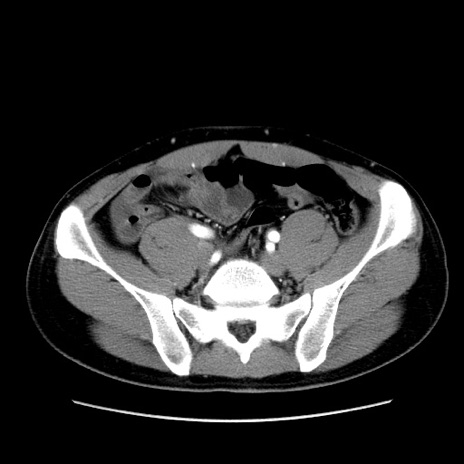

症例36(横断像)

【症例】20歳代 男性

【主訴】心窩部痛

【現病歴】今朝より上腹部痛あり。一旦軽快していたが再度出現したため救急要請。昨日夕に白身の魚を含む刺身を食べた。

【身体所見】BP 136/89mmHg、HR 74/min、BT 37.0℃、腹部:膨満、軟、心窩部に圧痛あり。反跳痛なし、筋性防御なし、腸雑音やや亢進あり。

【データ】WBC 17700、CRP 0.48